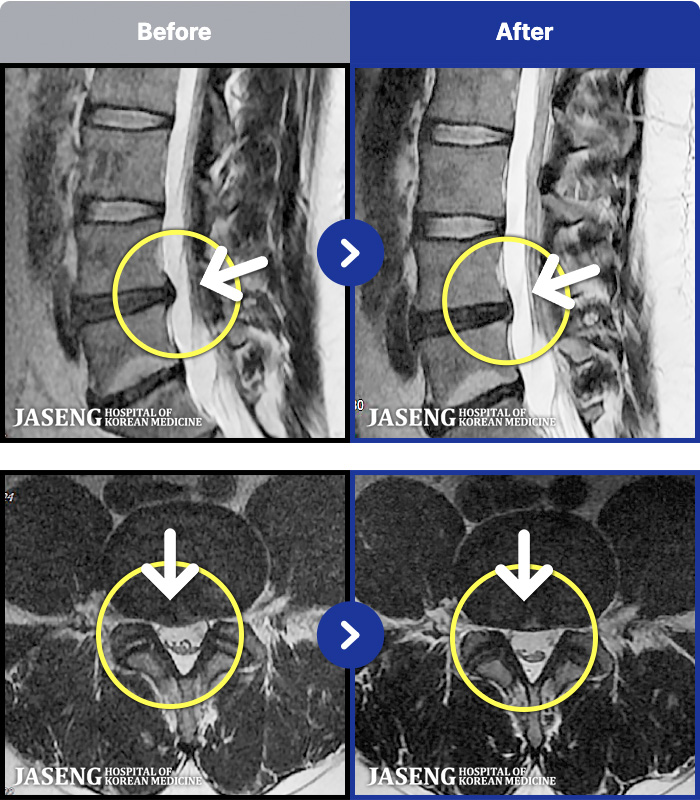

MRI ġ

MRI ũ ʸ Ȯϼ.

Ƹ ϰ ־.

[õ] 25.03.18~25.07.22

ȯںп Ǹ ǿ ԿǾ, ο ġ ۿ Ƿ ġḦ Ͻñ ٶϴ.